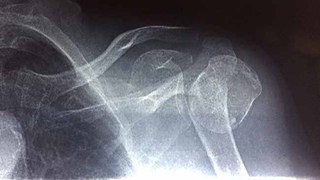

Today I fitted my elderly patient with her (hopefully) semi-permanent shoulder cast. This woman came into the clinic a few weeks ago. I remember treating her knee pain and when the visit was finished, she said, “What about my bone problem?” and pointed at her shoulder.

This is a classic pattern at our clinic. Right as patients are leaving, they add on a few extra problems and ask for medicine for it. I have to tell them to talk to me about it next time they come in. So, I told this patient to bring her x-rays and we would treat it next time. I assumed it was just arthritis in the shoulder. WRONG.